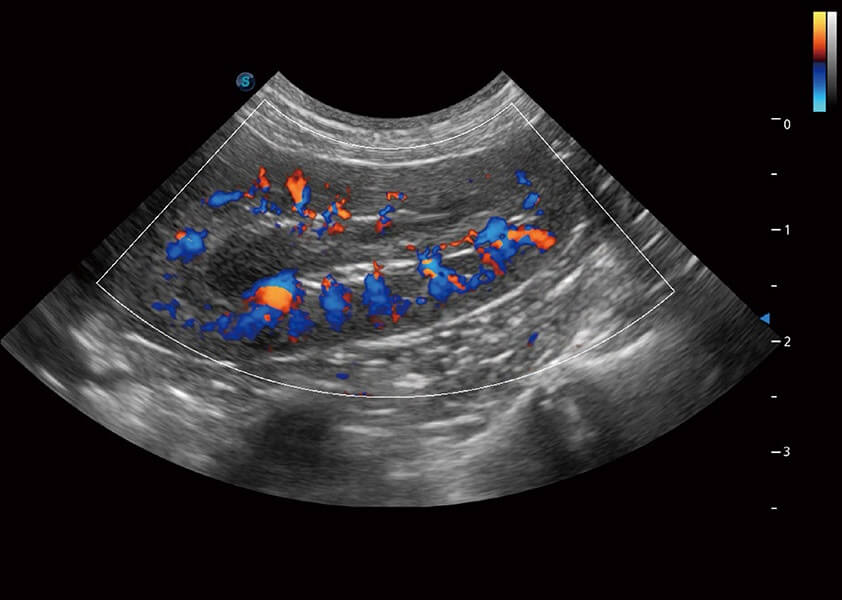

ProPet 60 作為一款高端臺(tái)式動(dòng)物超聲設(shè)備,為動(dòng)物醫(yī)生的日常診斷提供了一系列貼合動(dòng)物臨床需求、解決臨床實(shí)際問(wèn)題的高級(jí)成像功能。憑借全系列高清探頭,滿(mǎn)足醫(yī)生對(duì)腹部、心臟、生殖、淺表、肌骨等成像的所有需求,切實(shí)幫助您提升檢查效率,提高診斷信心。